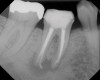

Figure 7  Clinical case of internal root resorption that was treated by orthograde root canal therapy.

Figure 7

Figure 8  Clinical case of internal root resorption that was treated by orthograde root canal therapy.

Figure 8